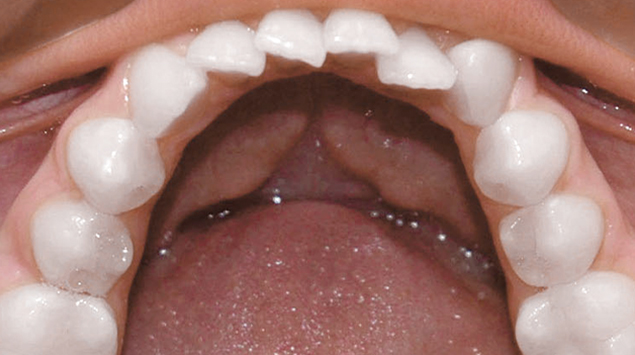

>   Stripping całego łuku dolnego w przypadku braku miejsca dla zębów. Pacjent bez usuwania zębów.